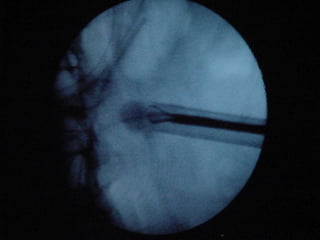

O documento discute o tratamento de urolitíase, especificamente a remoção de cálculos renais através de nefrolitotripsia. A cirurgia aberta é agora muito restrita devido aos avanços da ESWL e procedimentos endourológicos menos invasivos como ureteroscopia e cirurgia percutânea. A cirurgia laparoscópica está substituindo a cirurgia aberta como técnica menos invasiva que combina a tecnologia endourológica com a laparoscópica preservando